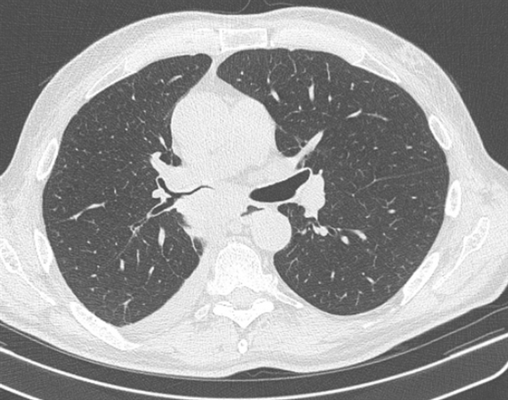

(а) Пациент, перенесший правостороннюю нижнедолевую лобэктомию. При рентгенографии органов грудной клетки в /7/7 проекции определяются объемное уменьшение правого легкого и смещение корня правого легкого вниз.

(б) У этого же пациента на совмещенных изображениях при КТ с контрастным усилением в легочном (слева) и мягкотканном (справа) режимах визуализируются объемное уменьшение правого легкого и хирургические скобы в области резекции. Оптимальным диагностическим ориентиром выполненной лобэктомии является выявление культи бронха и отсутствие резецированной доли легкого.